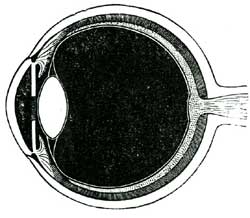

| XXV. | How we Hear, See, Smell, Taste; and Feel | 138 |